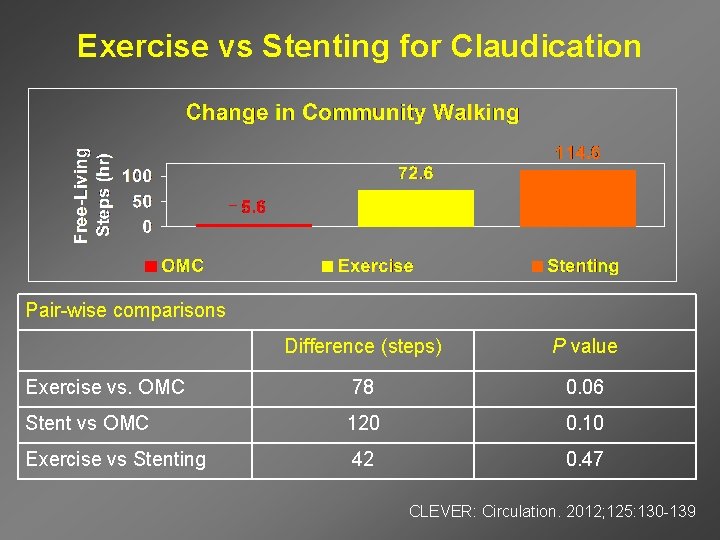

Exercise vs Stenting for Claudication _ Pair-wise comparisons Difference (steps) P value Exercise vs. OMC 78 0. 06 Stent vs OMC 120 0. 10 Exercise vs Stenting 42 0. 47 CLEVER: Circulation. 2012; 125: 130 -139